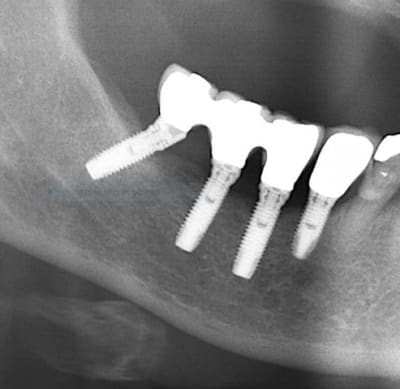

Identification implant

je ne suis pas sur a 100%, pour identifier ces implant.

Branemark??

Nobel mk3

https://whatimplantisthat.com/implants/details/branemark-mk-iii-np

et un speedy pour l'implant en 4 (ou 5....bref le plus antérieur)